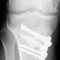

Die Rheumachirurgie hat einen großen Schwerpunkt in der Handchirurgie. Ziel ist es durch operative Maßnahmen die Gelenkfunktion wieder herzustellen, Sehnen- und Gelenkentzündungen zu entfernen (Bild 1 und 2), Stabilisierungsoperationen (Bild 3 Handgelenksversteifung, Bild 4 Fingerendgliedsversteifung) oder zerstörte Gelenkfunktionen wieder gangbar zu machen (Bild 5  Kernspin eines entzündeten Daumensattelgelnks, Bild 6 Röntgenbild nach Entfernung des Daumensattelgelenkes). Individuell müssen wir einen Behandlungsplan erstellen und eine Strategie entwickeln, ihre Hand-/ Fingerfunktion zu verbessern.